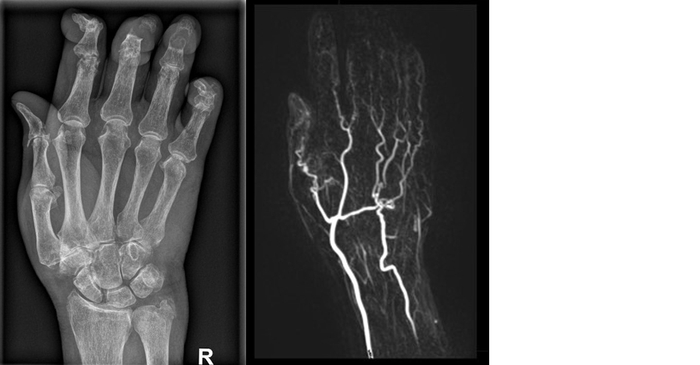

Röntgendarstellung und MRT-Darstellung einer Hand, die Rheuma aufweist

Röntgendarstellung (links) einer rheumatisch erkrankten Hand und MRT-Gefäßdarstellung mit Kontrastmittel (rechts).